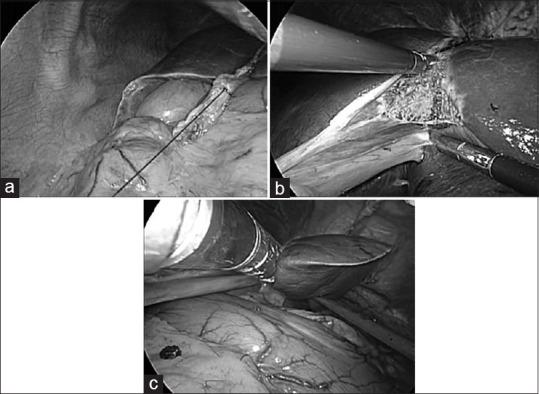

All patients who underwent LLS at Toranomon Hospital (Tokyo, Japan) were included, except for patients with a previous history of upper abdominal surgery or those who had undergone the simultaneous resection of another organ. An essential point of this procedure was the extracorporeal traction of the divided round ligament using a ligature. As a result, the operator was able to perform the parenchymal transection within a good operative field.

纳入所有在东京日本东京都虎之门医院接受LLS手术的患者,但既往有上腹部手术史或同时切除其他器官的患者除外。该手术的一个关键点是使用结扎线对离断的圆韧带进行体外牵引。这样一来,术者能够在良好的手术视野内进行实质离断。